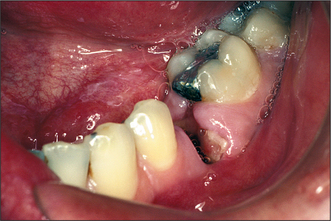

Osteonecrosis of the jaw (ONJ)

It has become apparent since about 2002 that patients taking bisphosphonate drugs (such as zoledronate, alendronate and pamidronate), which reduce bone resorption, are at risk of developing osteonecrosis, particularly after tooth extraction. The condition is recognized as failure to heal, exposure of dead bone (Fig. 4.32) and, often, associated infection. The condition persists with bone remaining exposed and failing to sequester for many months or years. Stopping use of the drug does not appear to make much difference to the outcome, probably because the half-life of the drugs, in the bone, is of the order of months to years. Tooth extraction should, if possible, be avoided in patients taking these drugs.

image

Fig. 4.32 Osteonecrosis of the jaw secondary to extraction of lower anterior teeth in a patient taking a bisphosphonate drug.